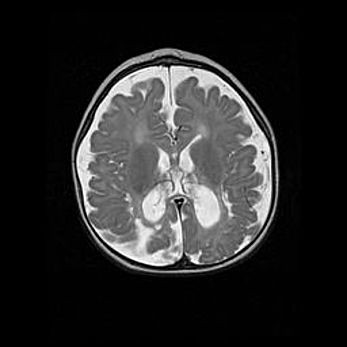

Множественные кисты обоих полушарий головного мозга, наибольшая из них в правой затылочной области. Ассиметричная атрофическая гидроцефалия.

Возраст: 7 месяцев

Вес: 5660 г

Пол: мужской

Окружность головы: 41,5 см

Срок гестации: 28-29 недель

Кисты головного мозга развиваются в результате многоочаговых некрозов вещества мозга и возникают вследствие перенесенной перинатальной инфекции, менингитов, энцефалитов, асфиксии, родовой травмы, расстройств мозгового кровообращения различного генеза. Образованию кист в веществе головного мозга плодов и новорожденных способствуют такие факторы, как высокое содержание в нем воды, недостаточная (или отсутствие) миелинизация и слабая астроглиальная реакция на повреждение.

Кисты могут сочетаться с гидроцефалией и другими поражениями головного мозга.